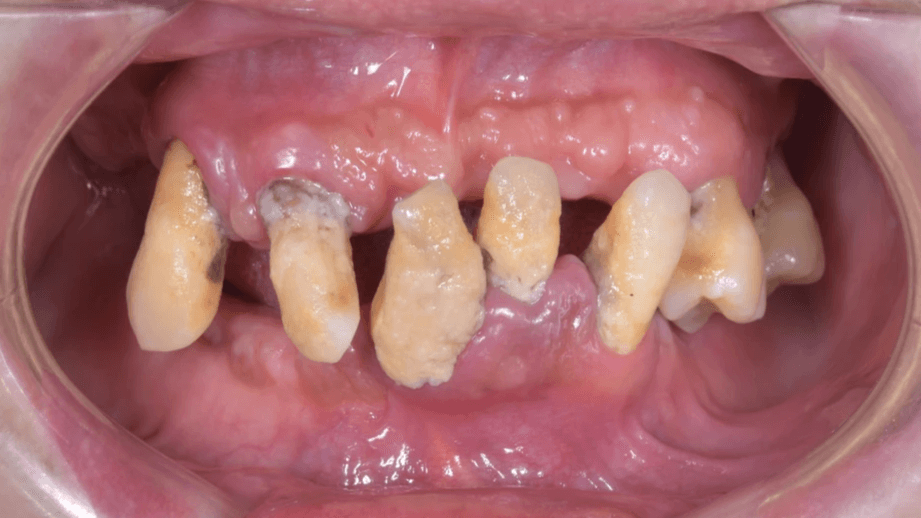

經詳細檢查後發現:

• 多顆牙齒已無法保留

• 骨頭吸收明顯

• 牙周狀況差

• 咬合已經不成形